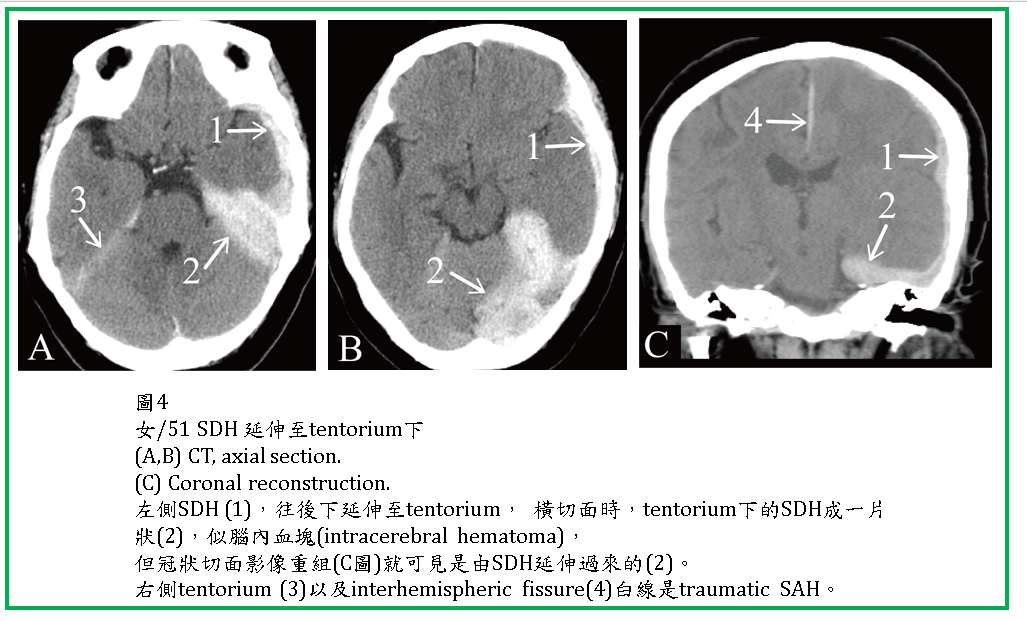

ASDH有時往後會延伸到小腦天幕下的硬腦膜下腔(圖1-3)。在CT橫切面,小腦天幕下SDH呈現片狀,極易被誤為是腦內血塊(ICH) (圖3,4)。SDH有時會在大腦半球間裂(interhemispheric fissure) (圖5),或由大腦額頂葉外的SDH滲透進入interhemispheric fissure 。